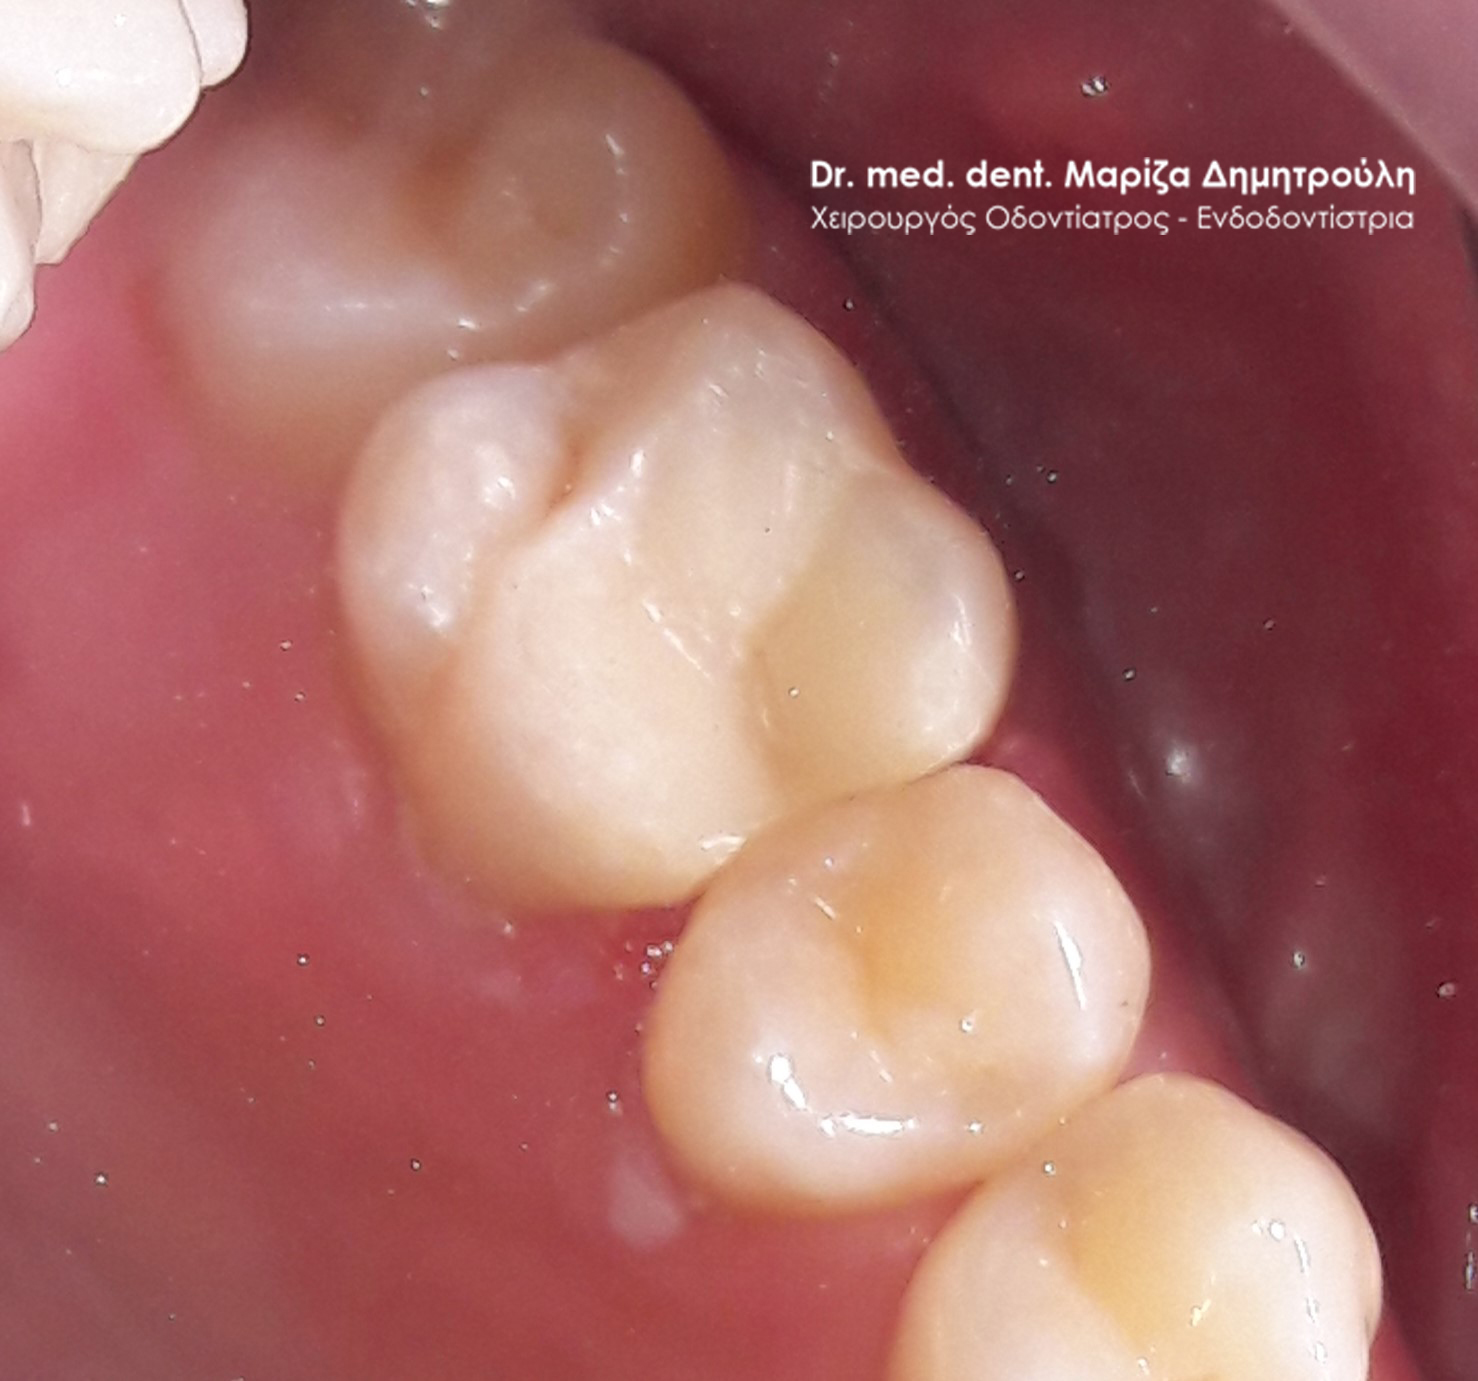

Περιστατικό – Απονεύρωση και σφραγίσματος δοντιού

Ο ασθενής επισκέφτηκε το ιατρείο με σκοπό την αποκατάσταση μιας “τρύπας” που αντιλήφθηκε από μόνος του. Μετά την κλινική εξέταση διαπιστώθηκε μία τερηδονική βλάβη στον αριστερό πρώτο γομφίο. Παρόλο που η κοιλότητα δεν ήταν μεγάλη σε πλάτος η τερηδόνα εκτεινόταν έφτανε σε μεγάλο βάθος στο ύψος του πολφού, δηλαδή του νεύρου του δοντιού. Ξεκίνησε η διαδικασία της απονεύρωσης δοντιού και μετά την ολοκλήρωση της πραγματοποιήθηκε λευκό σφράγισμα σύνθετης ρητίνης. Η αποκατάσταση του δοντιού πραγματοποιήθηκε με σφράγισμα και όχι με θήκη δοντιού, γιατί το έλλειμμα του δοντιού δεν ήταν τόσο μεγάλο ώστε να απαιτείται η κατασκευή στεφάνης για την προστασία του.

ΠΡΙΝ

Απονεύρωση δοντιού

Αποκατάσταση δοντιού με προσωρινό σφράγισμα μετά το τέλος της απονεύρωσης

Τελικό λευκό σφράγισμα